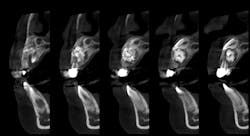

A panoramic film (figure 1) taken by the general dentist revealed a large radiodense area in the region apical to teeth D and E. The patient was referred to an oral and maxillofacial surgeon who obtained a CBCT scan (figure 2).

Clinical and radiographic assessment revealed retained primary teeth D and E, and buccal cortical expansion over the apices of these teeth. A cone beam CT scan revealed a well circumscribed, mixed radiodensity overlying the apices of the primary teeth, adjacent permanent teeth nos. 7 and 8 displaced in a caudal direction, and cortical expansion.